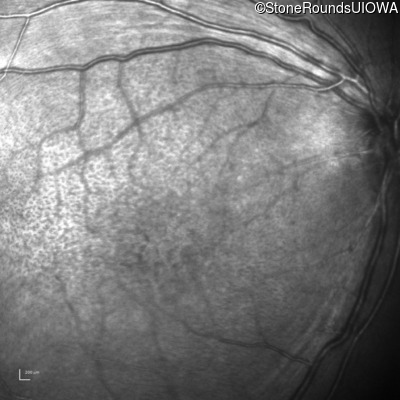

Infrared Fundus Photograph - Left - 10/40

Exemplar